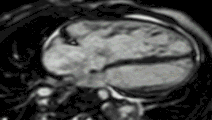

Enlarged right ventricle with poor function in a patient with repaired tetralogy of Fallot by CMR